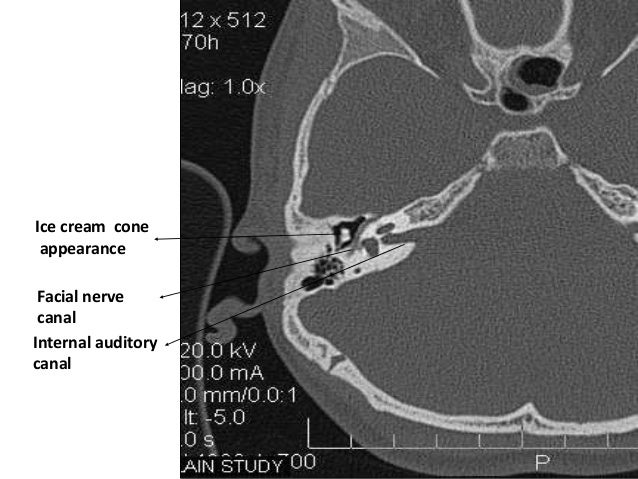

- HRCT Temporal bone anatomy

- Planes of scanning Axial 30 Degrees to anthropological base line Parallel to lateral SCC. Best displays inner & middle ear. ...

- EAR IS DIVIDED INTO 3 PARTS • EXTERNAL EAR • MIDDLE EAR • INTERNAL EAR 5 EAC Tympanic cavity Bony & membranous labyrinth

CT and MRI are primarily used for imaging of the temporal bone. We first present the standard technique and protocols most often used, then review the special considerations for both modalities. A brief overview of the roles of plain radiographs, ultrasound (US), positron emission tomography (PET), and PET/CT is given at the end of this section.

CT arteriography (CTA) or CT venography (CTV) of the temporal bone may be used to evaluate for tinnitus. At our institution, the standard CT protocol for temporal bone imaging is employed, but the injection rate is increased to 3 to 4 cc per second for CTA. A power injector is employed if a 22-gauge IV or larger is available.